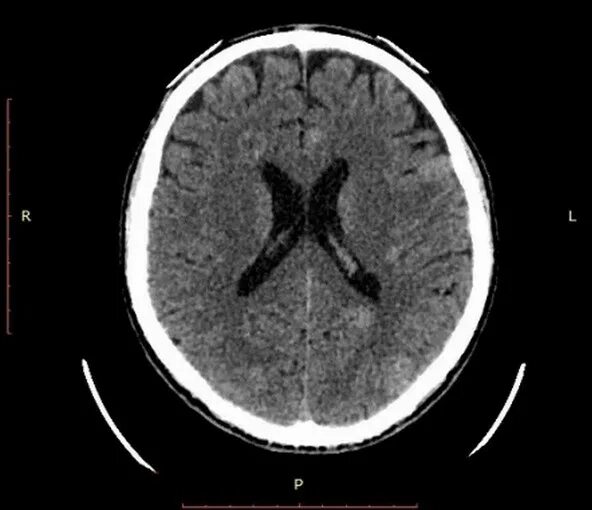

Метастазы головного мозга кт